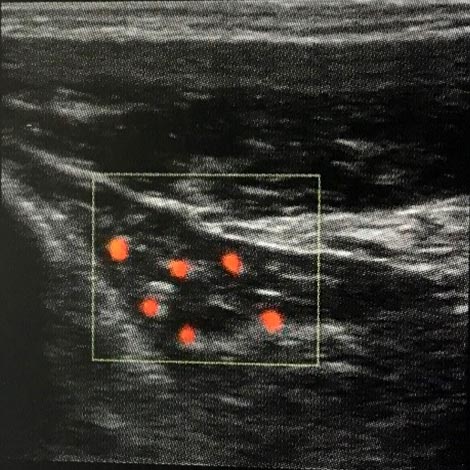

Sonographisch kann mittels power Doppler imaging(PDI)aus der Zahl der abgebildeten irregulären Gefäße auf die Anzahl der Nozizeptoren geschlossen werden. Hier beispielsweise typisch für degenerierte schmerzhafte Sehnenansatzerkrankungendie Epicondylitis lateralis (Tennisarm) und die entzündete Achillessehne (Achillodynie).

PDI Aufnahme: Epicondylitis lateralis, Neovaskularisation in der Sehne des M.extensor carpi radialis brevis.